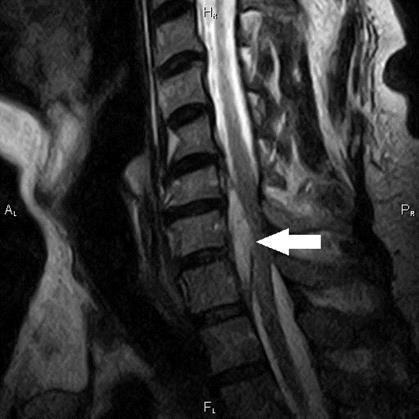

| Abcesul epidural | DEFINIȚIE ȘI CAUZE Abcesul spinal epidural se poate forma oriunde de-a lungul canalului spinal.

Factorii de risc pentru abcesul epidural sunt reprezentați de afectarea stării imune în diverse afecțiuni ca diabetul zaharat, alcoolism, insuficiența renală, tumori maligne. Alte elemente care pot cauza un abces sunt infecțiile cu diferite localizări sau administrarea intravenoasă a drogurilor. SIMPTOMATOLOGIETabloul clinic e reprezentat de triada: durere, febră și pareza rapid progresivă. DIAGNOSTICDintre examenele imagistice, IRM localizează cel mai bine abcesul. TRATAMENTÎn cazul abceselor mici, tratamentul este medicamentos și constă în administrarea de antibiotice per os sau injectabil. Antibioticoterapia va fi în conformitate cu rezultatele hemoculturilor. În cazul abceselor de dimensiuni mari, cu fenomene compresive, se va interveni chirurgical. Tratamentul chirurgical constă din laminectomie decompresivă și debridare. Pre și postoperator se va administra un antibiotic pentru cel puțin 4 saptamani.